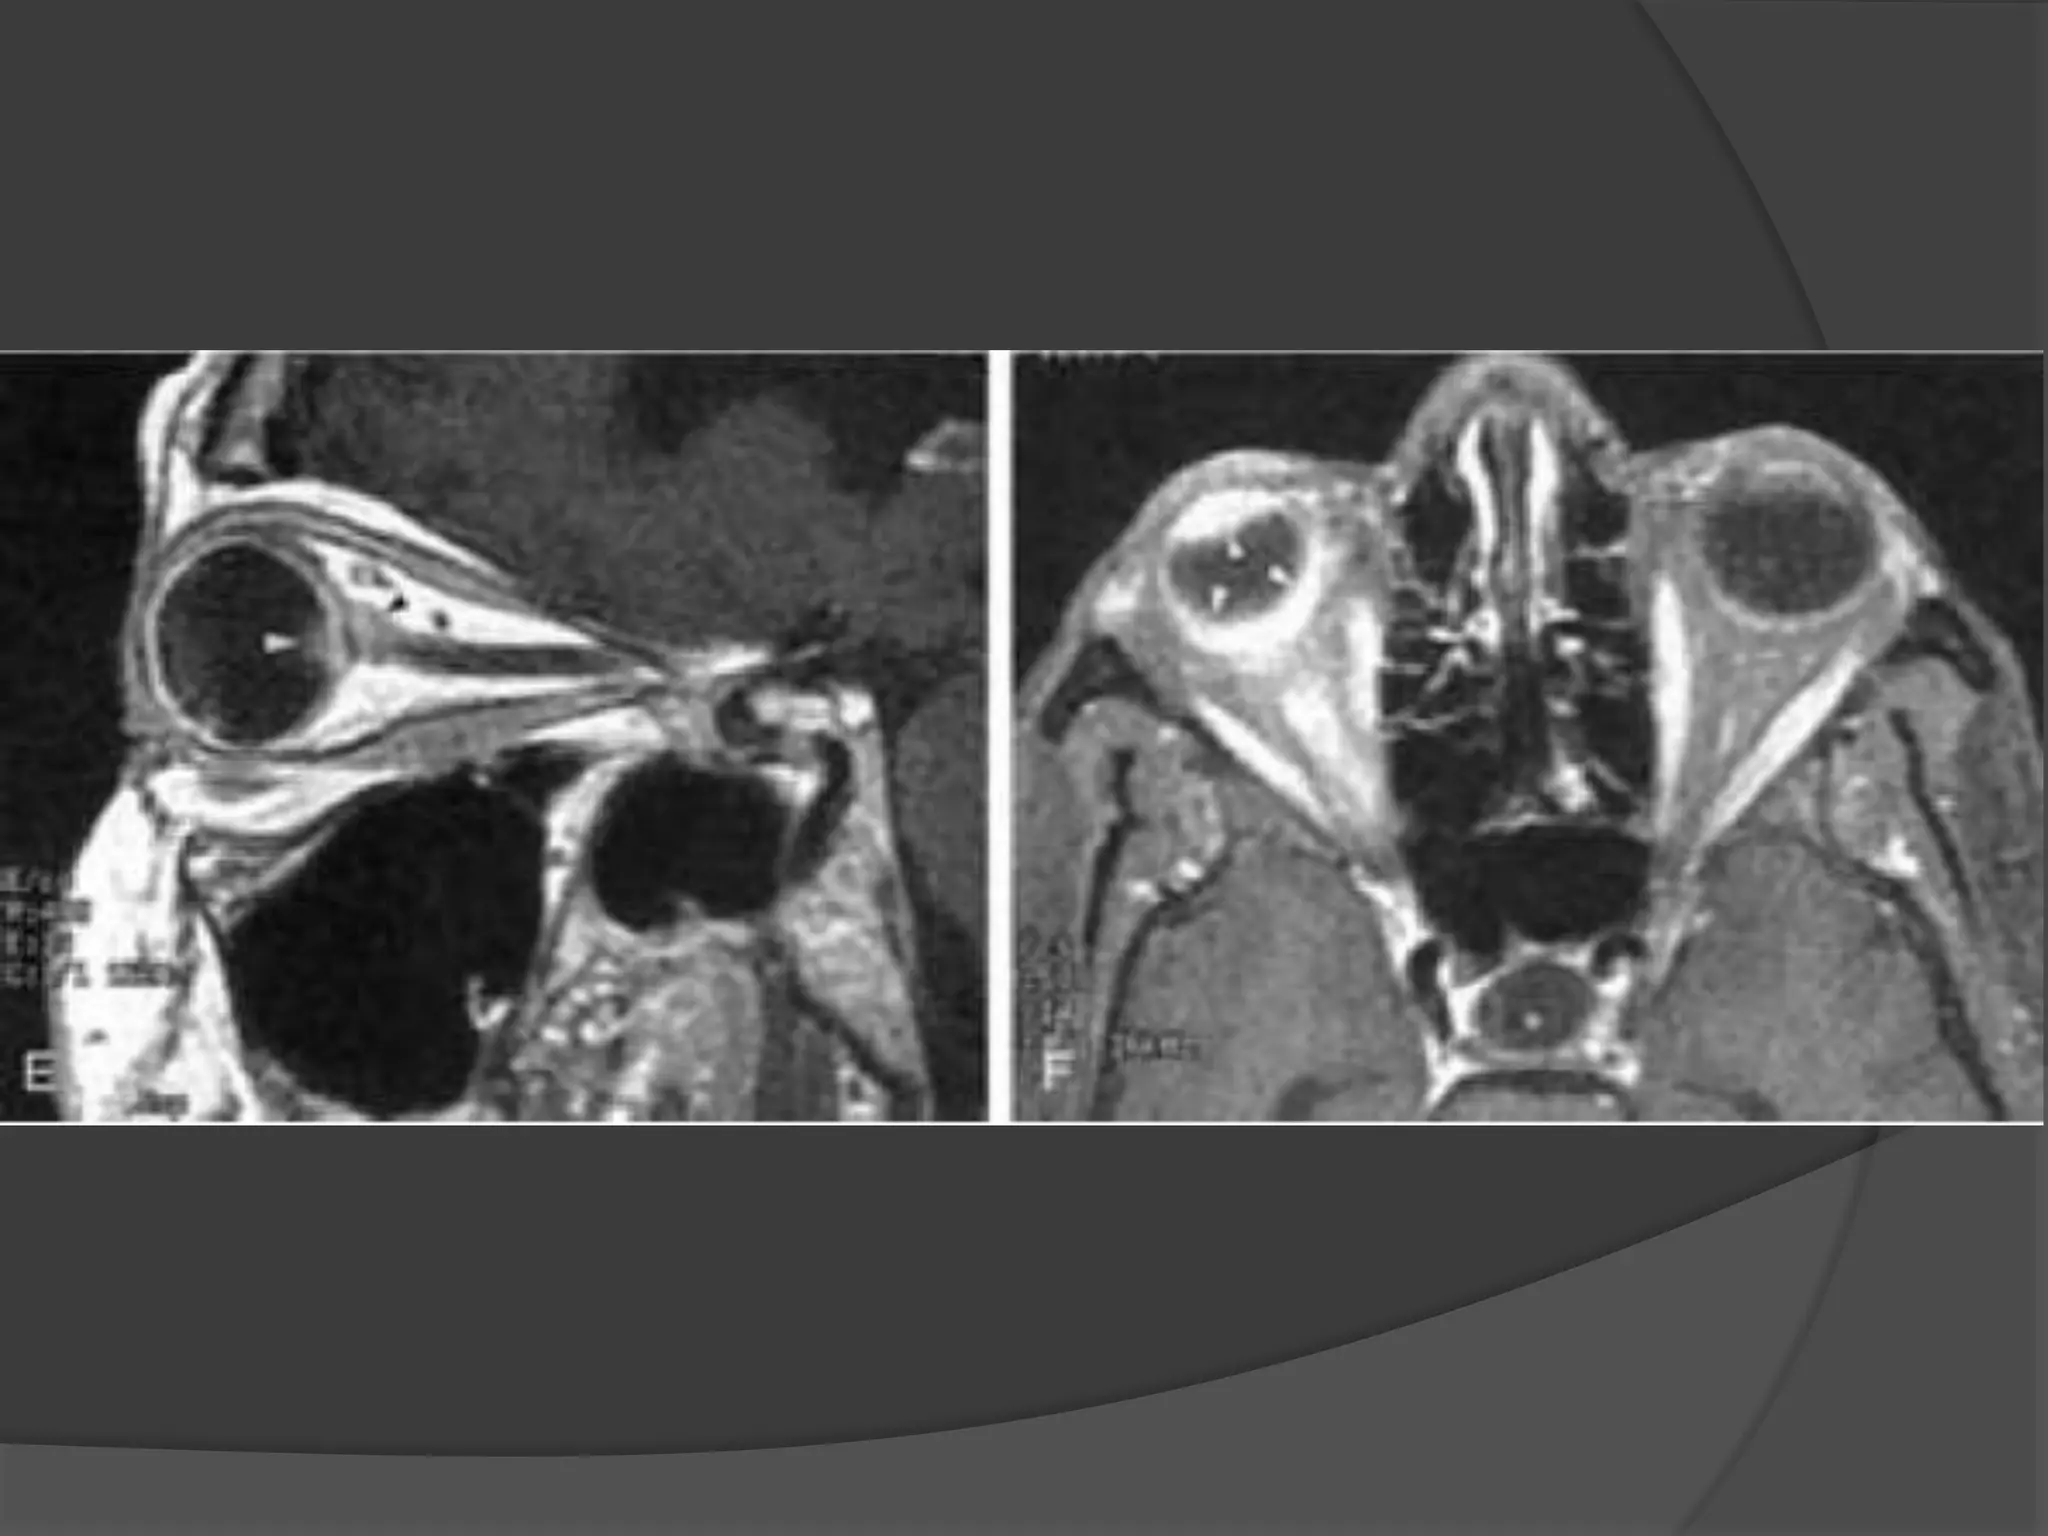

• #21 Granulomatous uveitis. A, Axial T2WI shows hypointense lesions (arrows). B, Axial enhanced, T1WI shows marked enhancement of the entire uveal tract (arrow). C, Unenhanced axial T1-WI shows nodular thickening of the posterior aspect of the right globe (arrow) and thickening of the anterior segment (arrowheads) of the right globe. D, Enhanced axial fat-suppressed, T1WI shows nodular enhancement of the posterior aspect of the right globe (arrowhead and open arrow) related to granulomatous involvement of the choroids.

• #22 Granulomatous uveitis. E, Enhanced sagittal T1WI shows granuloma at the optic disc (white arrowhead) as well as involvement of the optic nerve (black arrowhead ). F, Enhanced axial fat-suppressed, T1WI shows enhancement of the markedly thickened uveal tract (arrowheads).